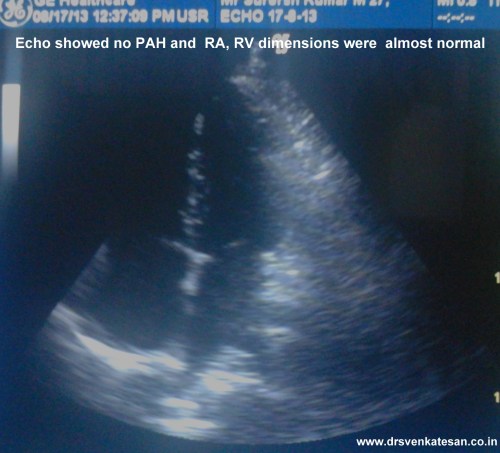

A 25 year man ,  hotel  manager  who had a documented DVT , since 2011 was on tablet warfarin . He discontinued  the drug by sheer miscommunication as he was told he should stop the  drug  beyond INR 3 by his general practitioner.He stopped it permanently  instead of titrating the dose of warfain .Six months later he landed  in August 2013 with an episode of minor hemoptysis . Clincally he was normal .His lower limbs were fine.

He was investigated and  his image file showed .

Living with one lung

• He is comfortable with one lung function (Akin to  Pneumonectomy )

• His saturation was 100 % at room air

• Pulse -80/mt .BP 110/80mmhg

• His physical activity  did  not show any significant limitation (At worst class 2)

One of the cardiac surgery consultant wanted to do pulmonary embolectomy and endarteriectomy .

In fact , he was admitted in the critical care unit driven by the dramatic CT images.

One enthusiastic cardiologist wanted  thrombus aspiration and pig tail catheter based thrombolytic  irrigation within LPA !

How did we manage ?

• The risk of major vascular surgery was considered high in an absolutely asymptomatic individual .

• Intervention was considered too adventurous.

• He was  put on oral anticoagulant with target  INR 2.5-3.(After a 1 week Heparin overlap)

• We hope the thrombotic CTO will open up gradually but for surely .As the power of  natural lytic  molecules should not be underestimated as we have witnessed in LV and LA clot disappearing over months.

• However the option of putting IVC filter was strongly recommended for him , as he has only  functioning  lung  which  is threatened by a potential  embolus from DVT . The patient wanted to come back for IVC filter next month.

• He was also worked up for all those protein C, S,  Lieden mutation stuff.

• The patient was discharged in stable condition (By the way he  was never unstable either !)

* Meanwhile the hemoptysis  did not recur. CT scan showed a small wedge infarct in left lung that was in the healing mode.

Final message

This is a perfect example of  CTO of pulmonary artery being  managed conservatively* .We will let you know the follow up .